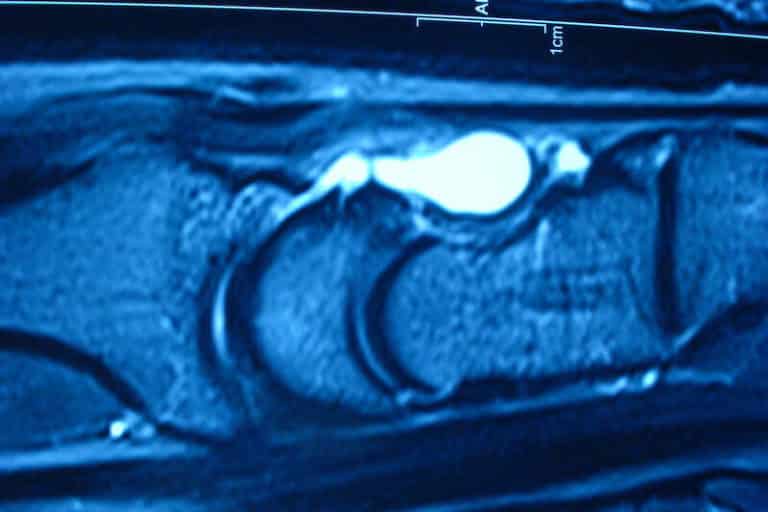

La boule au poignet : qu'est-ce que c'est ? Encore appelée le kyste synovial du poignet, la boule au poignet est une poche qui contient un liquide visqueux, gélatineux et assez transparent appelé : le liquide synovial.Elle se développe généralement dans les tissus et organes du corps, notamment au niveau des articulations.Il faut noter cependant que, cette bosse ou cette grosseur qui. Il peut aussi tester la fonctionnalité de l'articulation et rechercher d'éventuels signes de compression des nerfs. Qu'est-ce qu'une bosse au poignet ? Une bosse du poignet est une protubérance ou une bosse anormale sur le poignet

Kyste synovial du Diagnostic et opération Dr Roure. Cette dureté correspond à l'importance du remplissage du kyste synovial. Selon l'Institut français de chirurgie de la main, le premier signe du kyste synovial du poignet est l'apparition progressive ou.